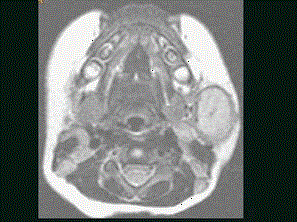

问题 40岁,患者,左面部渐进性增大的包块,MRI检查如图所示,应考虑为 ( )

选项 A、左面部脂肪瘤 B、左面部神经纤维瘤 C、左面部囊肿 D、左面部脓肿 E、左面部毛细血管瘤

答案 E